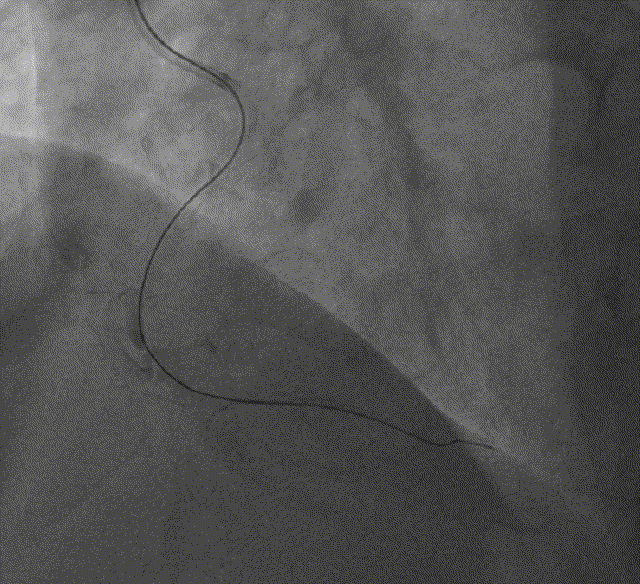

RCA开口畸形,第一转折长段不规则狭窄伴钙化最重约70%,自第二转折次全闭塞

XT-A导丝到位闭塞部位近端

XT-A+微导管顺利通过闭塞部位

● 指引导管SAL 1.0

● 术中微导管、穿通导管尝试均难以通过闭塞部位

● 缺少1.25、1.5球囊(集采、疫情导致小球囊供应短缺),Tazuna 2.0*15mm球囊掘进困难